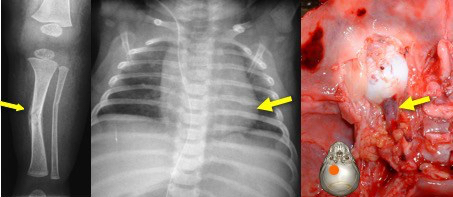

les autres lésions du SBS

il peut exister :

- des lésions osseuses : fractures de côtes quand l’enfant a été tenu par le thorax ; décollement périosté des membres

- des lésions du rachis et de la moelle, possiblement à l’origine d’un arrêt respiratoire qui aggrave l’anoxie cérébrale

- un hématome de la gaine du nerf optique